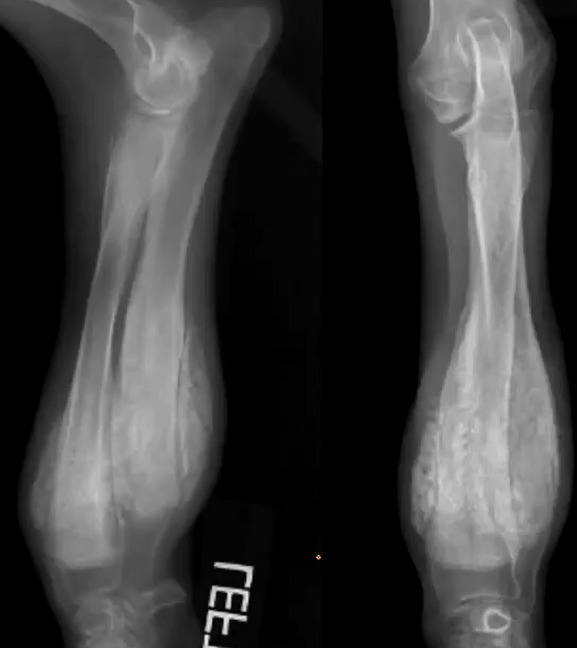

Describe panosteitis

Self limiting disease in large breed dogs that are 5-18 months old

What bones are affected with panosteitis?

Long bones

What are the early radiographic changes for panosteitis?

Increased medullary opacity

What are the middle radiographic changes of panosteitis?

Endosteal roughening, more defined opacities, mild periosteal reaction

What are the late/healed radiographic changes of panosteitis?

Hallow or lucent medullary canal, horizontal opaque bands